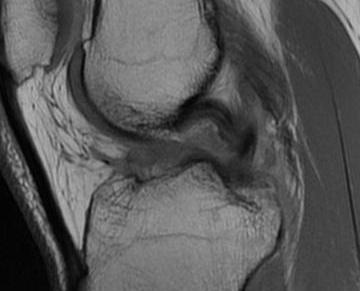

Bony Avulsion

Chronic bony avulsion PCL

Posterior subluxation of tibia

Grade 3 PCL disruption - posterior tibia subluxed behind posterior aspect femoral condyles

MRI

PCL completely torn

PCL midsubstance tear with lengthening

PCL tibial avulsion

PCL femoral avulsion